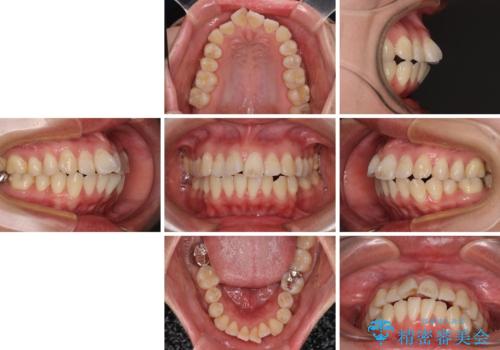

- 上下の出っ歯を気にして来院された患者様です。

口元を積極的に引っ込めるために、上下左右の第一小臼歯を4本抜歯することとしました。

また、上下前歯は舌の突出癖による開咬となっていたため、舌のトレーニングを徹底するよう指示しました。

舌突出癖の改善トレーニングは、仕上がり、治療期間、そして治療後の後戻りに大きな影響を及ぼします。

トレーニングをしっかりと行っていただいたため、スッキリとした口元に仕上がりました。